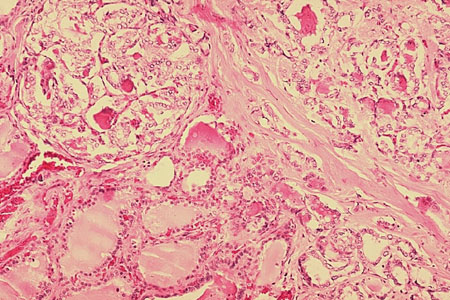

Oncocytic carcinoma (previously known as Hürthle cell carcinoma): presence of tumour cells within a vein, indicative of vascular invasion

Sandoval MAS et al. Case Reports 2011;2011:bcr1120103536; used with permission

See this image in context in the following section/s: